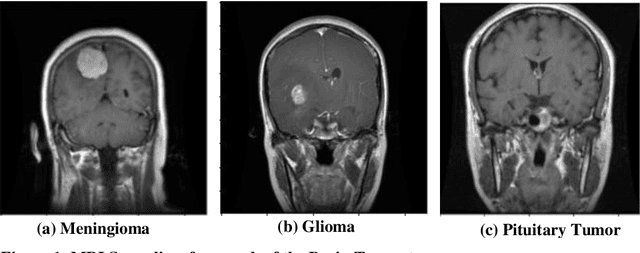

Abstract:Brain Tumors are abnormal mass of clustered cells penetrating regions of brain. Their timely identification and classification help doctors to provide appropriate treatment. However, Classifi-cation of Brain Tumors is quite intricate because of high-intra class similarity and low-inter class variability. Due to morphological similarity amongst various MRI-Slices of different classes the challenge deepens more. This all leads to hampering generalizability of classification models. To this end, this paper proposes HSADML, a novel framework which enables deep metric learning (DML) using SphereFace Loss. SphereFace loss embeds the features into a hyperspheric-manifold and then imposes margin on the embeddings to enhance differentiability between the classes. With utilization of SphereFace loss based deep metric learning it is ensured that samples from class clustered together while the different ones are pushed apart. Results reflects the promi-nence in the approach, the proposed framework achieved state-of-the-art 98.69% validation accu-racy using k-NN (k=1) and this is significantly higher than normal SoftMax Loss training which though obtains 98.47% validation accuracy but that too with limited inter-class separability and intra-class closeness. Experimental analysis done over various classifiers and loss function set-tings suggests potential in the approach.